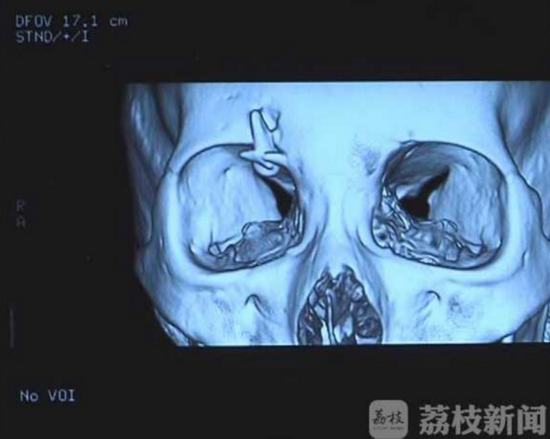

江蘇省中醫院神經外科醫生傅傳經說,從片子來看,在婷婷右側眼眶的上緣,能看到一個類似于牙齒形狀的異物,結合對方患者的門牙,高度懷疑異物就是個牙齒。由于牙齒釉質比骨頭密度還要高,牙齒前面也是比較銳利的,如果相撞的時候,正好是銳口對骨頭,這個瞬間牙齒是能夠將骨頭戳穿,卡進入骨頭里的。婷婷的母親說,電動車相撞時,對方確實缺損了三顆門牙,當時也沒有找到門牙的去處。今天中午,婷婷在江蘇省中醫院神經外科接受了手術,在避免損傷周圍的視覺神經的前提下,醫生將卡在眉骨上的牙齒取下來。